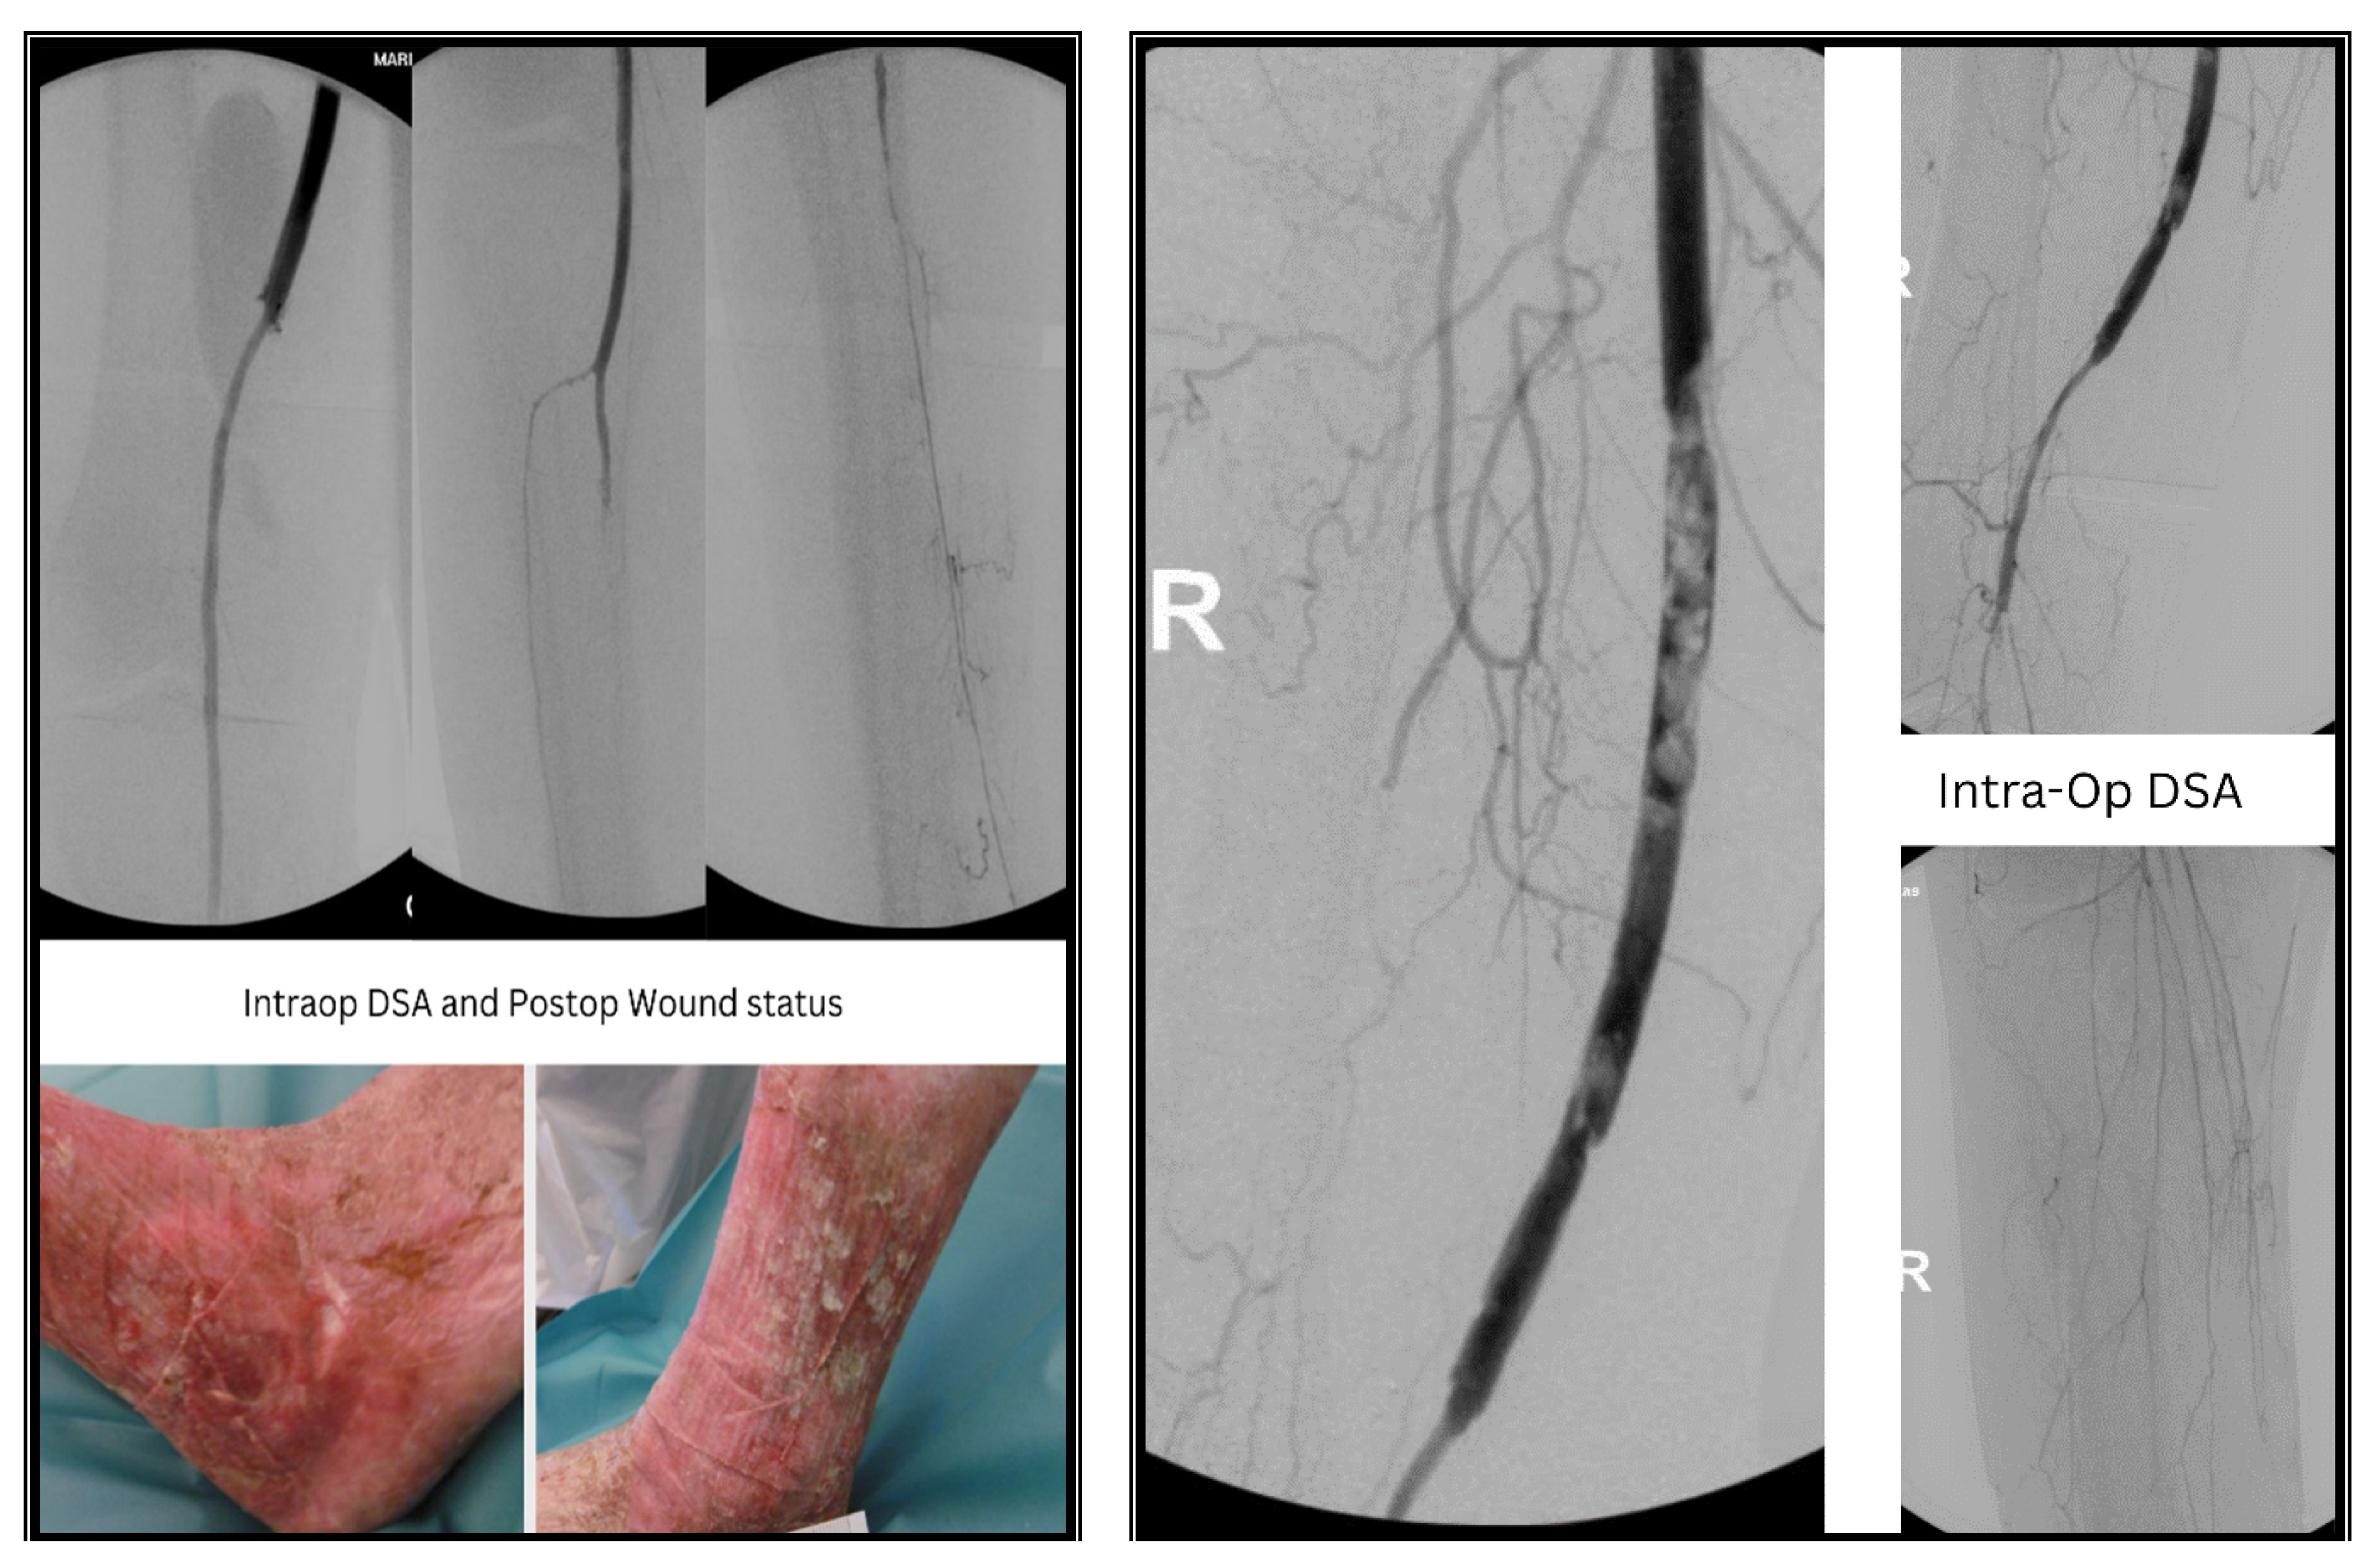

3.2. Case II